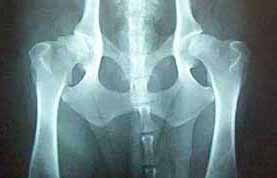

Medical X-rays